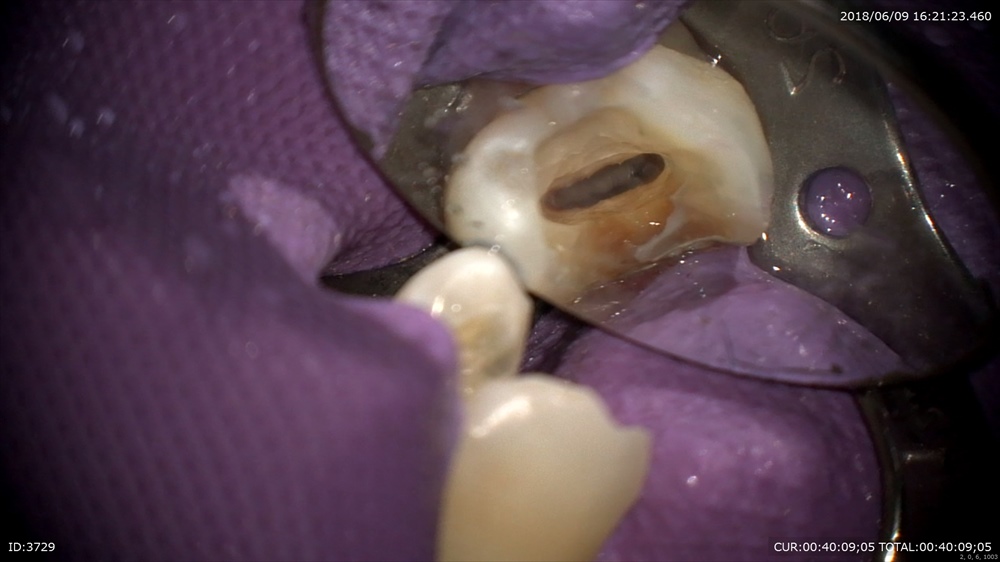

精密検査で

根尖性周囲炎と診断し

金属を外し根管治療

綺麗に無痛で

お薬をいれ今日は終了